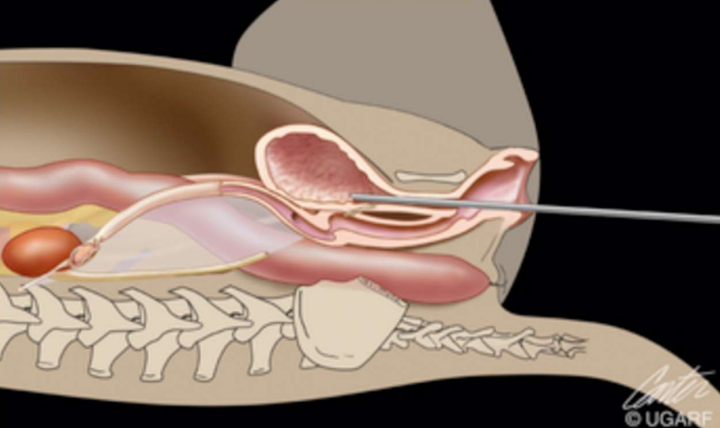

| Urine sampling & handling (소변의 채취와 취급) | - 가장 이상적인 채취 : cystocentesis (방광 천자) - 드물게 urethral catheterization(카테터 사용)으로 대체 - 이상적인 보관 : UTT (urine culture transport tubes) + preservative (보존제) - 24시간 내 실험실 수송 권장 (보존제 있어도 <48H) - 기본 요검사는 보존제 없이 syringe 보관해도 됨. |

| Contrast radiographs _Prostatitis | |

|---|---|

| - 전립선 비대 - 농양 - 배뇨곤란 |

| Ultrasonography (Abd) | _Prostatitis |

|---|---|

| - 전립선의 비대와 mild한 hyperechogenecity부터, - 심각한 비대와 mottled hyperechoic~hypoechoic pattern (얼룩덜룩한 패턴) 까지 다양함. - mottled sign → 감염, 종양 있을 때 |